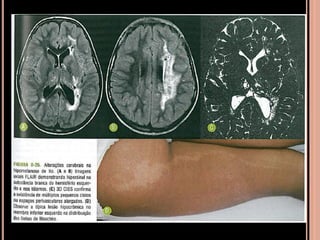

 Isquemia cerebral crônica –atrofia cortical

lentamente progressiva com calcificações

distróficas girais;

SÍNDROME DE STURGE-WEBER

Crises epilépticas Retardo mental

Nevo facial de cor do

“vinho do Porto”

 Nevo presente desde o nascimento e localiza-se

no dermátono do nervo trigêmio;

 Principalmente crises epilépticas: devido à

circulação anormal;

 Atraso no desenvolvimento...

SSW

Recomendações

 RM com contraste (T1 ou FLAIR pós gadolínio);

 TC: calcificações girais (mas dispensável); não

aparecem antes dois 2 anos; Se suspeita procurar

os achados mais consistentes;